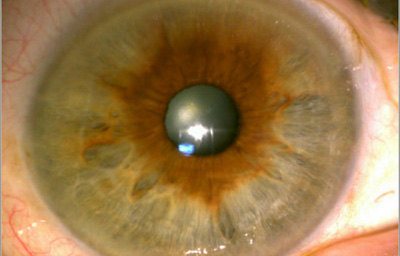

En la cara Anterior esta el pigmento que le da el color al Iris y dependiendo del grado de reabsorción u atrofia de esa capa anterior se pueden observar:

Las Criptas de Fuchs: que son pequeñas aberturas alrededor del collarete, producto de la atrofia o reabsorción de la hoja anterior del iris, que le permiten al estroma y a los tejidos mas profundos estar en contacto con el humor acuoso.

Cuando el Iris no tiene criptas, se considera que la reabsorción u atrofia de la hoja anterior (memb. pupilar) se detuvo en el circulo menor.

El Color del Iris

El Iris en general es muy pigmentado con colores que comúnmente van del marrón, avellana, gris, verde y azul. Existen los iris sin pigmento en el Albinismo oculo-cutáneo en cuyo caso se ven blanco/rosados.

El color del Iris es un fenómeno complejo por efectos combinados por la textura, la pigmentación y el tejido fibrovascular del estroma, junto con la constitución epigenética del individuo. Desde el punto de vista óptico, la simple absorción o reflexión selectiva por algunas moléculas, como la hemoglobina o el colágeno del estroma que son componentes no pigmentados, puede tener influencia en el color que es observado.

A pesar de la gran variedad en el color del Iris, el único pigmento que contribuye en forma sustancial es la melanina; su cantidad, es uno de los factores que determina el color del iris en una persona. Estructuralmente el color depende de la cantidad variable de eumelanina (melaninas marron/negra) y pheomelanina (melaninas rojo/amarillo) producidas por los melanocitos derivados de la Cresta Neural. El grado de dispersión de la melanina que yace en racimos subcelulares en los melanosomas, tiene cierta influencia en el color que se observa, pero el grado de dispersión no es reversible ya que los melanosomas no son moviles.